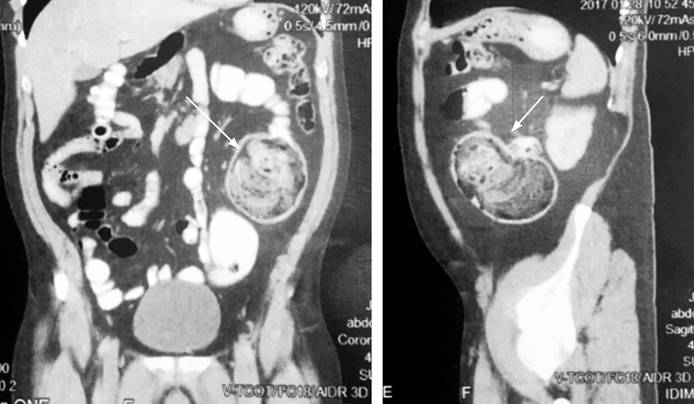

Se trata de un paciente masculino de 42 años, sin antecedentes patológicos relevantes. Consultó inicialmente por un cuadro de dos años de evolución de dolor en el hemiabdomen izquierdo, asociado a sensación de masa y hábito intestinal con períodos de estreñimiento y diarrea. Realizó múltiples consultas en las que le dieron manejo médico sin mejoría. De forma ambulatoria se realizó una colonoscopia con mala preparación colónica por la presencia de materia fecal en la unión rectosigmoidea. La tomografía axial computarizada (TAC) de abdomen con doble contraste reportó dolicosigma, ocupación de la unión colon-sigmoidea de material hipodenso y heterogéneo que alcanzaba un diámetro transverso de 8 cm, lo que hizo sospechar de impactación fecal segmentaria frente a un bezoar. Se realizó un TAC de control (Figura 1) en el Hospital Universitario San Ignacio, cuyos hallazgos sugirieron como primera posibilidad un bezoar en la luz del colon descendente distal, no asociado a obstrucción intestinal. Fue valorado por cirugía de colon y recto y se consideró que era un paciente con un divertículo gigante en el colon descendente, por lo que se realizó una resección y anastomosis por laparotomía, de forma prioritaria. Los hallazgos intraoperatorios (Figura 2) mostraron una lesión redondeada en el colon descendente, hacia el borde lateral de la cara antimesentérica de 10 x 8 cm de consistencia blanda. No cursó con complicaciones posoperatorias y al séptimo día se le dio egreso.

Figura 1 TAC con doble contraste, corte coronal y sagital (lesión señalada con flecha). Fuente: historia clínica del paciente.